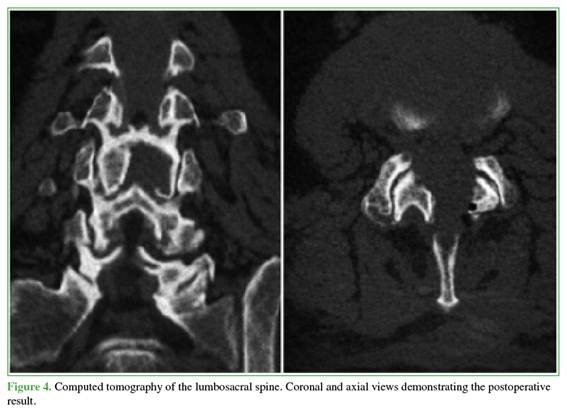

The findings were consistent with a hemorrhagic juxtafacet synovial cyst. Given the acute presentation with progressive motor neurological deficit and severe radicular compression, the patient underwent urgent decompression. The objective was to relieve neural compression, reverse the motor deficit, and allow rapid functional recovery while minimizing invasiveness. A posterior interlaminar uniportal endoscopic decompression was performed using a contralateral (left-sided) approach and the “over-the-top” technique (above the dural sac) to achieve safe and complete cyst resection (Figures 2-5).

The procedure lasted 95 minutes. Blood loss was minimal and not quantifiable, and no intraoperative complications occurred.

The patient had a favorable immediate postoperative course. Within the first 24 hours, pain improved markedly (2/10 on the visual analog scale), and motor recovery was incipient. He was discharged 24 hours after surgery with an outpatient physical therapy program. At the 7-day follow-up, ankle dorsiflexion strength had improved to 5/5.